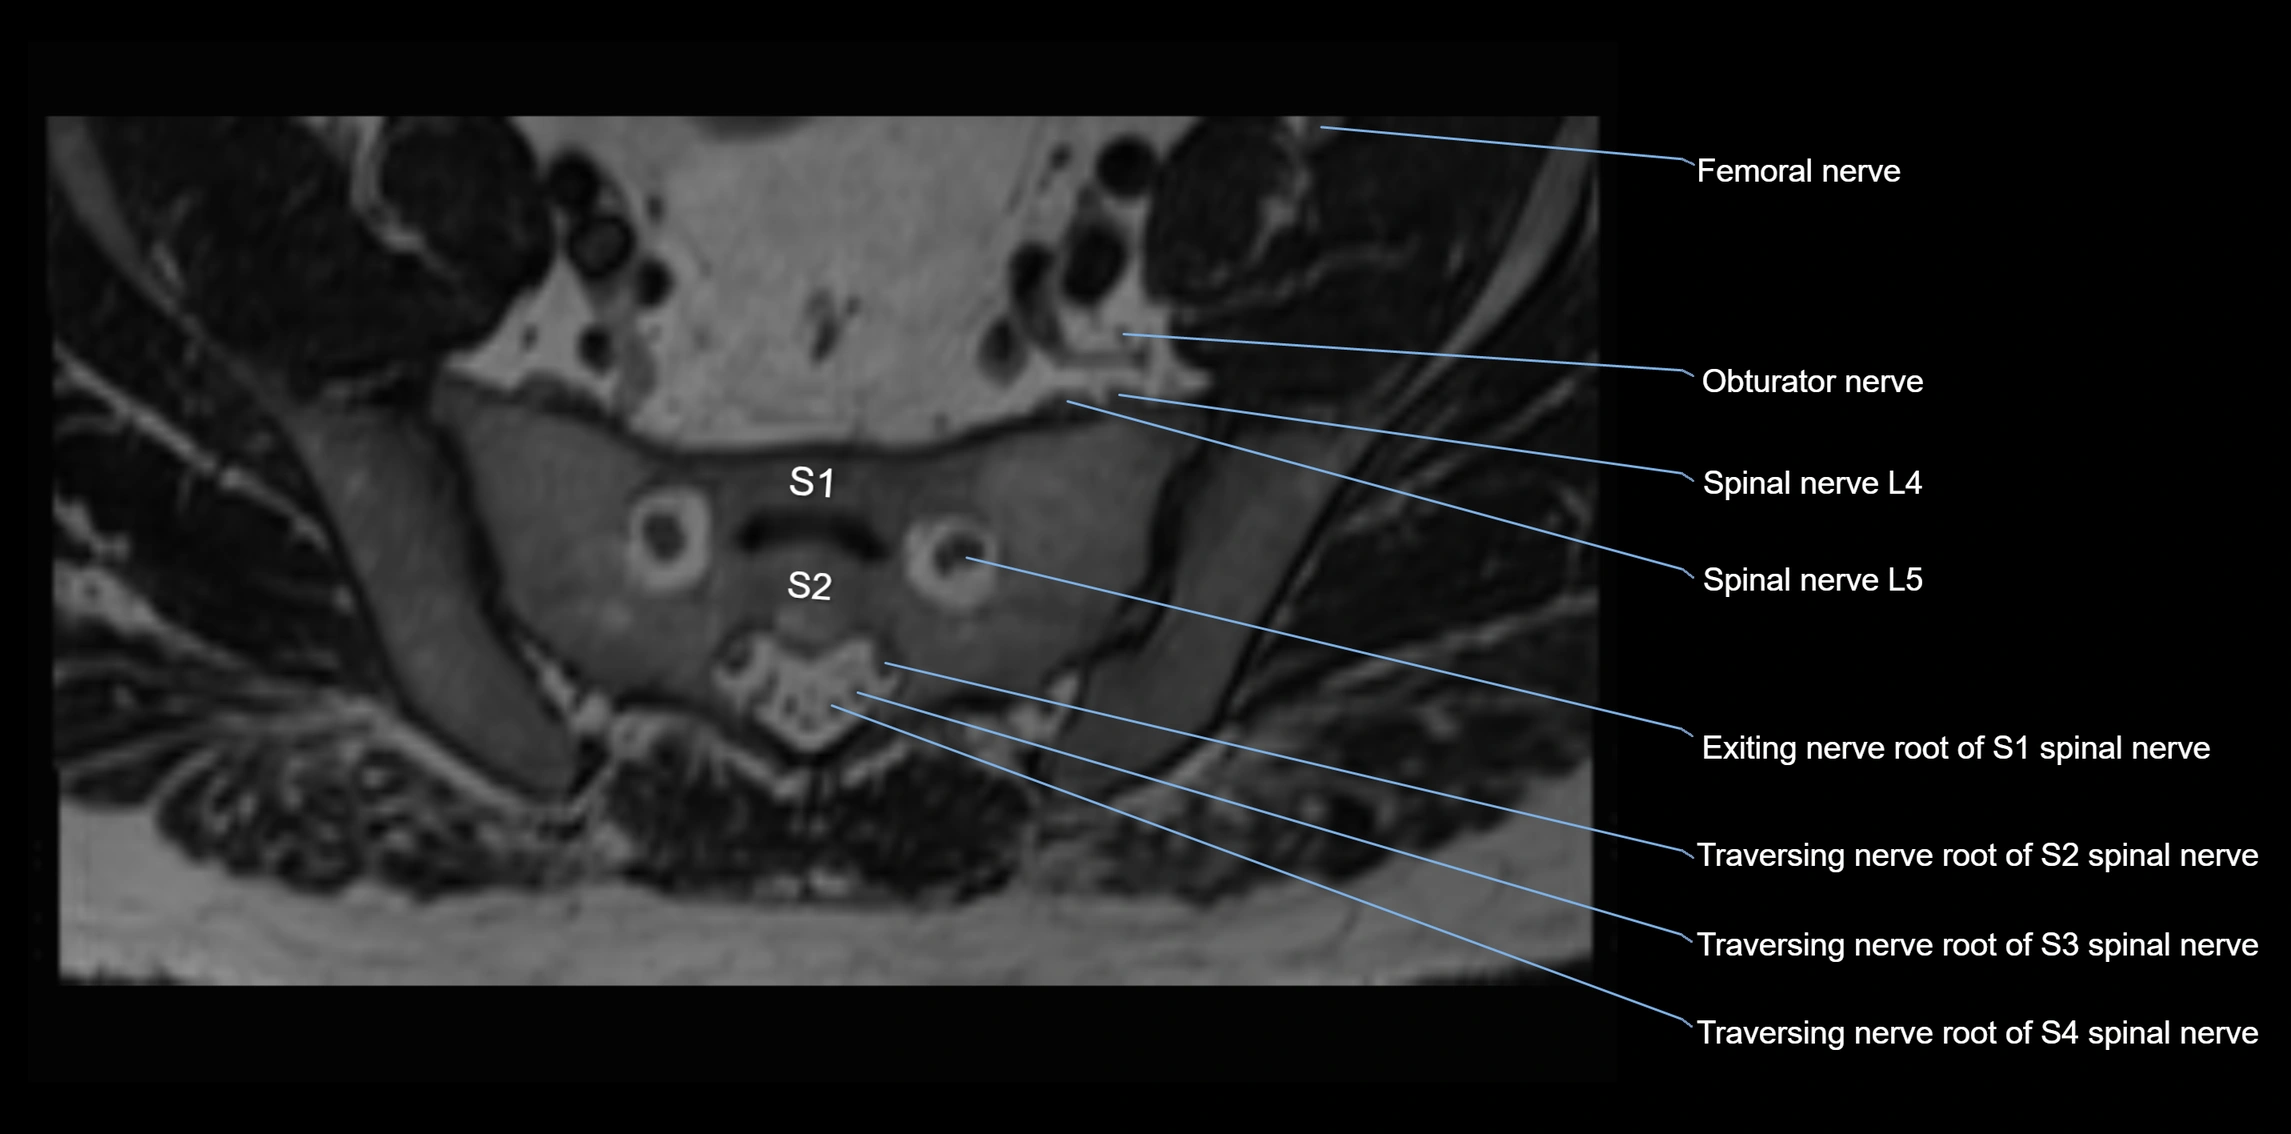

MRI image

image